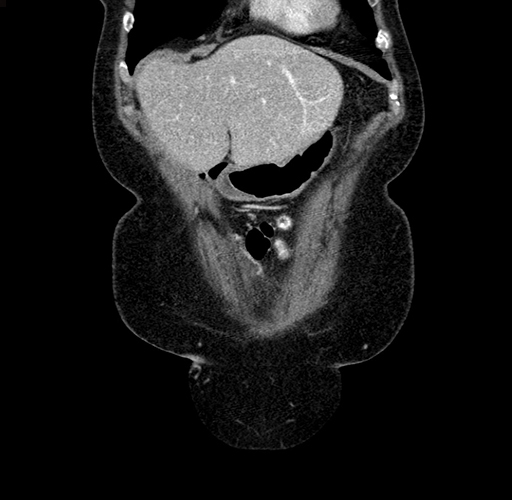

Pre-Chemo: Coronal Venous

Coronal Venous